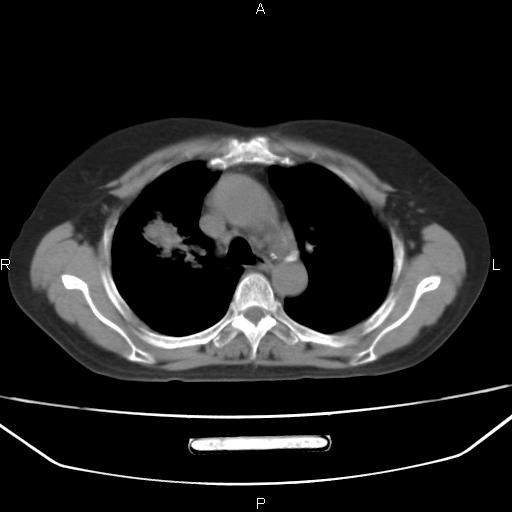

患者,女,66岁。健康体检胸部透视发现右上肺片状阴影。既往无不适,患者自诉三个月前曾有低热病史体温37.5左右一周。用药后缓解。至今无其它不适。请老师们指导指导。

考虑:右肺上叶周围型肺癌(分叶状肿块+砂粒状钙化+胸膜尾征)。

病灶见明显分叶、大小较大(大于3cm?),老年人,多考虑:肺癌,建议穿刺活检。

右肺上叶周围型肺癌可能性大。

考虑:右肺上叶周围型肺癌